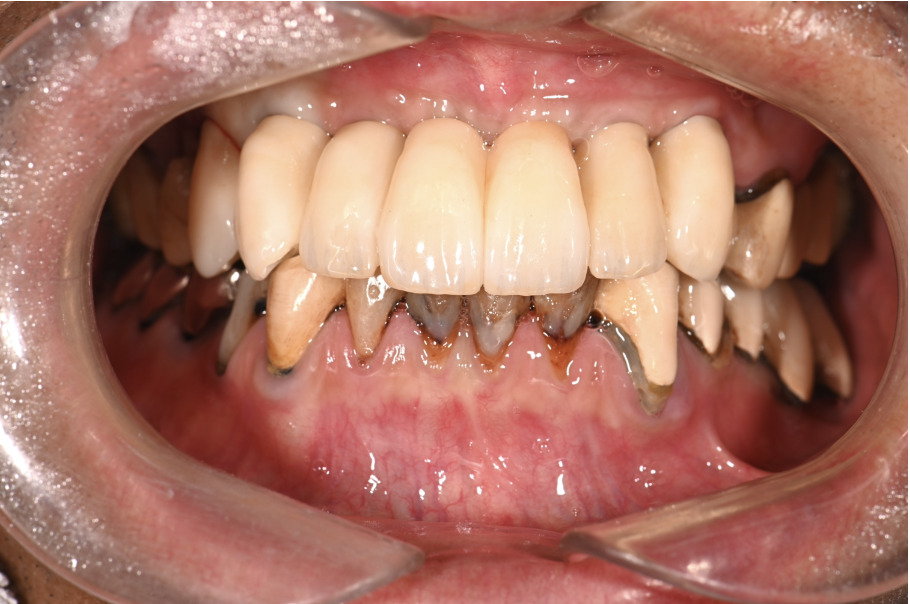

| 主訴 | 歯がグラグラして噛めない |

|---|---|

| 治療内容 | 上顎、下顎に対するインプラント治療 |

| 治療期間 | 1日 |

| 治療費 | 409万2千円 |

| 治療 リスク | 最終的な歯が入るまでは仮歯になります。 |